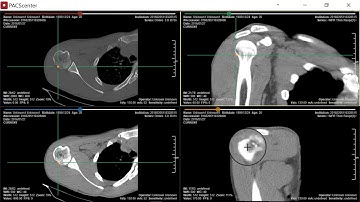

MPR-Synchronization | PACScenter Tutorial